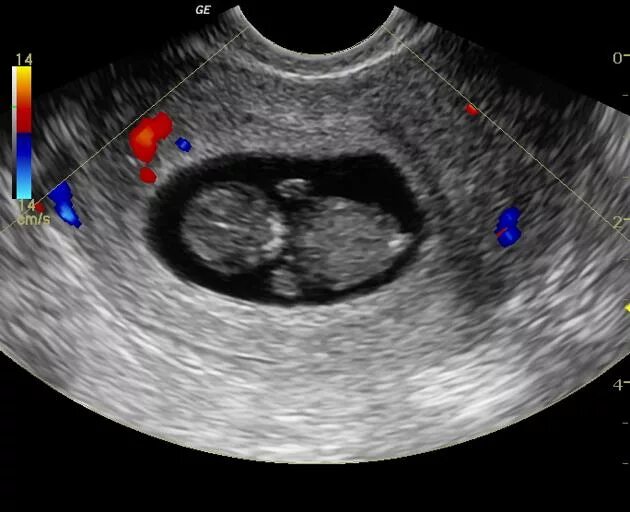

Может ли ошибки узи